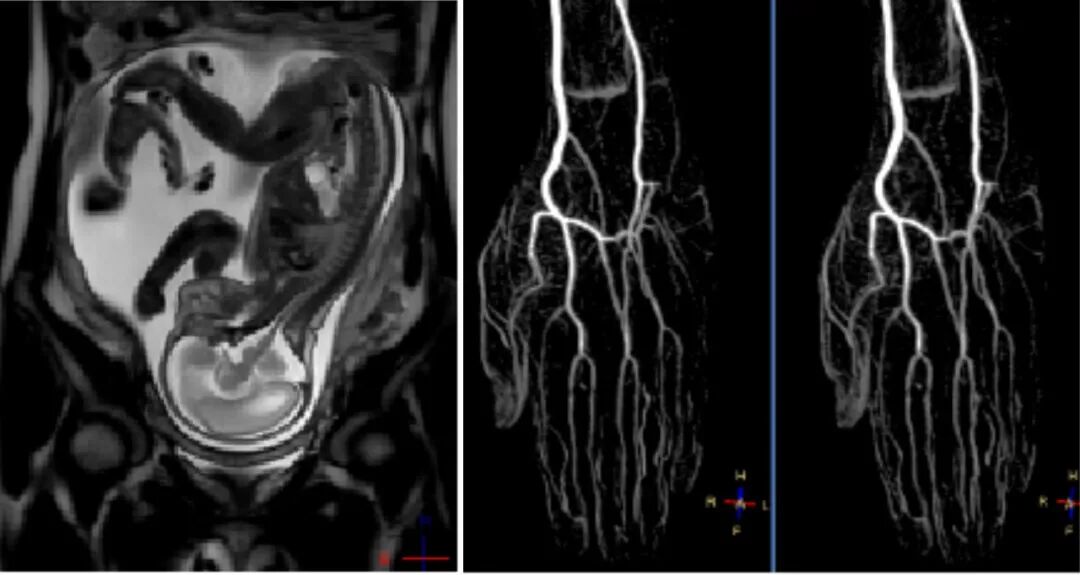

我院飞利浦1.5T磁共振(MRI)具有扫描速度快、成像效果清晰,后处理功能强大等优势,可以满足临床医师和患者的不同需求。磁共振应用广泛,主要用于人体各系统、各部位的肿瘤性病变、感染性病变、代谢性病变、先天畸形以及创伤性疾病的检查,对于神经系统、心血管、骨关节系统、肝脏、脾脏、胰腺、肾脏等腹部脏器以及前列腺、子宫等盆腔实质性脏器的检查独具优势。

我院购进的飞利浦胎儿四维彩超可以多方位、多角度地观察胎儿在子宫内的生长发育情况,实时显示胎儿的动态活动,如微笑、踢腿等可爱动作。